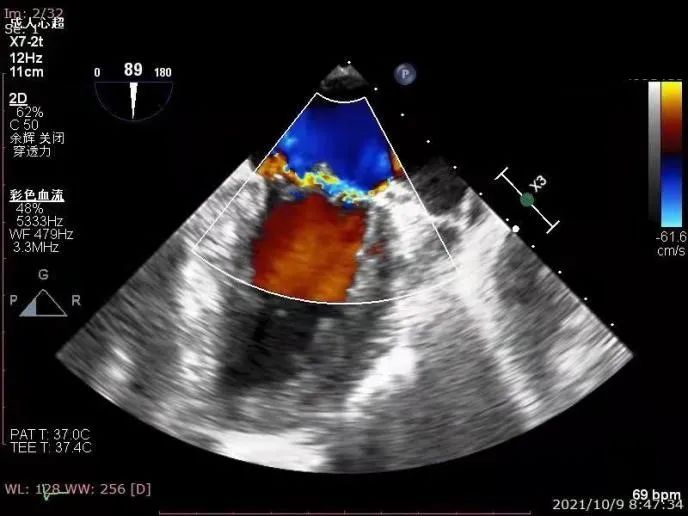

术前心超

患者全麻后,在超声和射线引导下器械经股静脉穿刺房间隔,通过输送系统送入患者左心房,顺利到达病变的二尖瓣区域。在经食道超声及DSA引导下,术者通过反复评估二尖瓣膜脱垂范围、抓捕位置、反流程度,精准夹合,成功植入一枚DragonFly瓣膜夹稳定脱垂瓣叶。患者术后反流从4+减少到1+,跨二尖瓣平均压差3mmHg,血流动力学改善明显,手术取得圆满成功。

二尖瓣重度关闭不全伴后叶脱垂(2区)、左房右房左室扩大、肺动脉高压(轻度)。